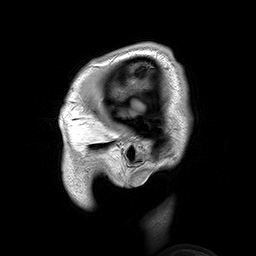

Dwayne Reed at English Wikipedia [CC BY-SA 3.0 (http://creativecommons.org/licenses/by-sa/3.0) or GFDL (http://www.gnu.org/copyleft/fdl.html)], via Wikimedia Commons

The orbitofrontal cortex is likely to be an important brain structure involved in the comparison between different types of goods (Dreher, 2009). Is there a common brain network associated with reward for many different types of goods and is that the obitofrontal cortex? If the evidence supports it and so far it seems to, the orbitalfrontal cortex is the economic network of the brain and economic value is processed there. The common neural currency is the common brain network which is activated by primary and secondary rewards.